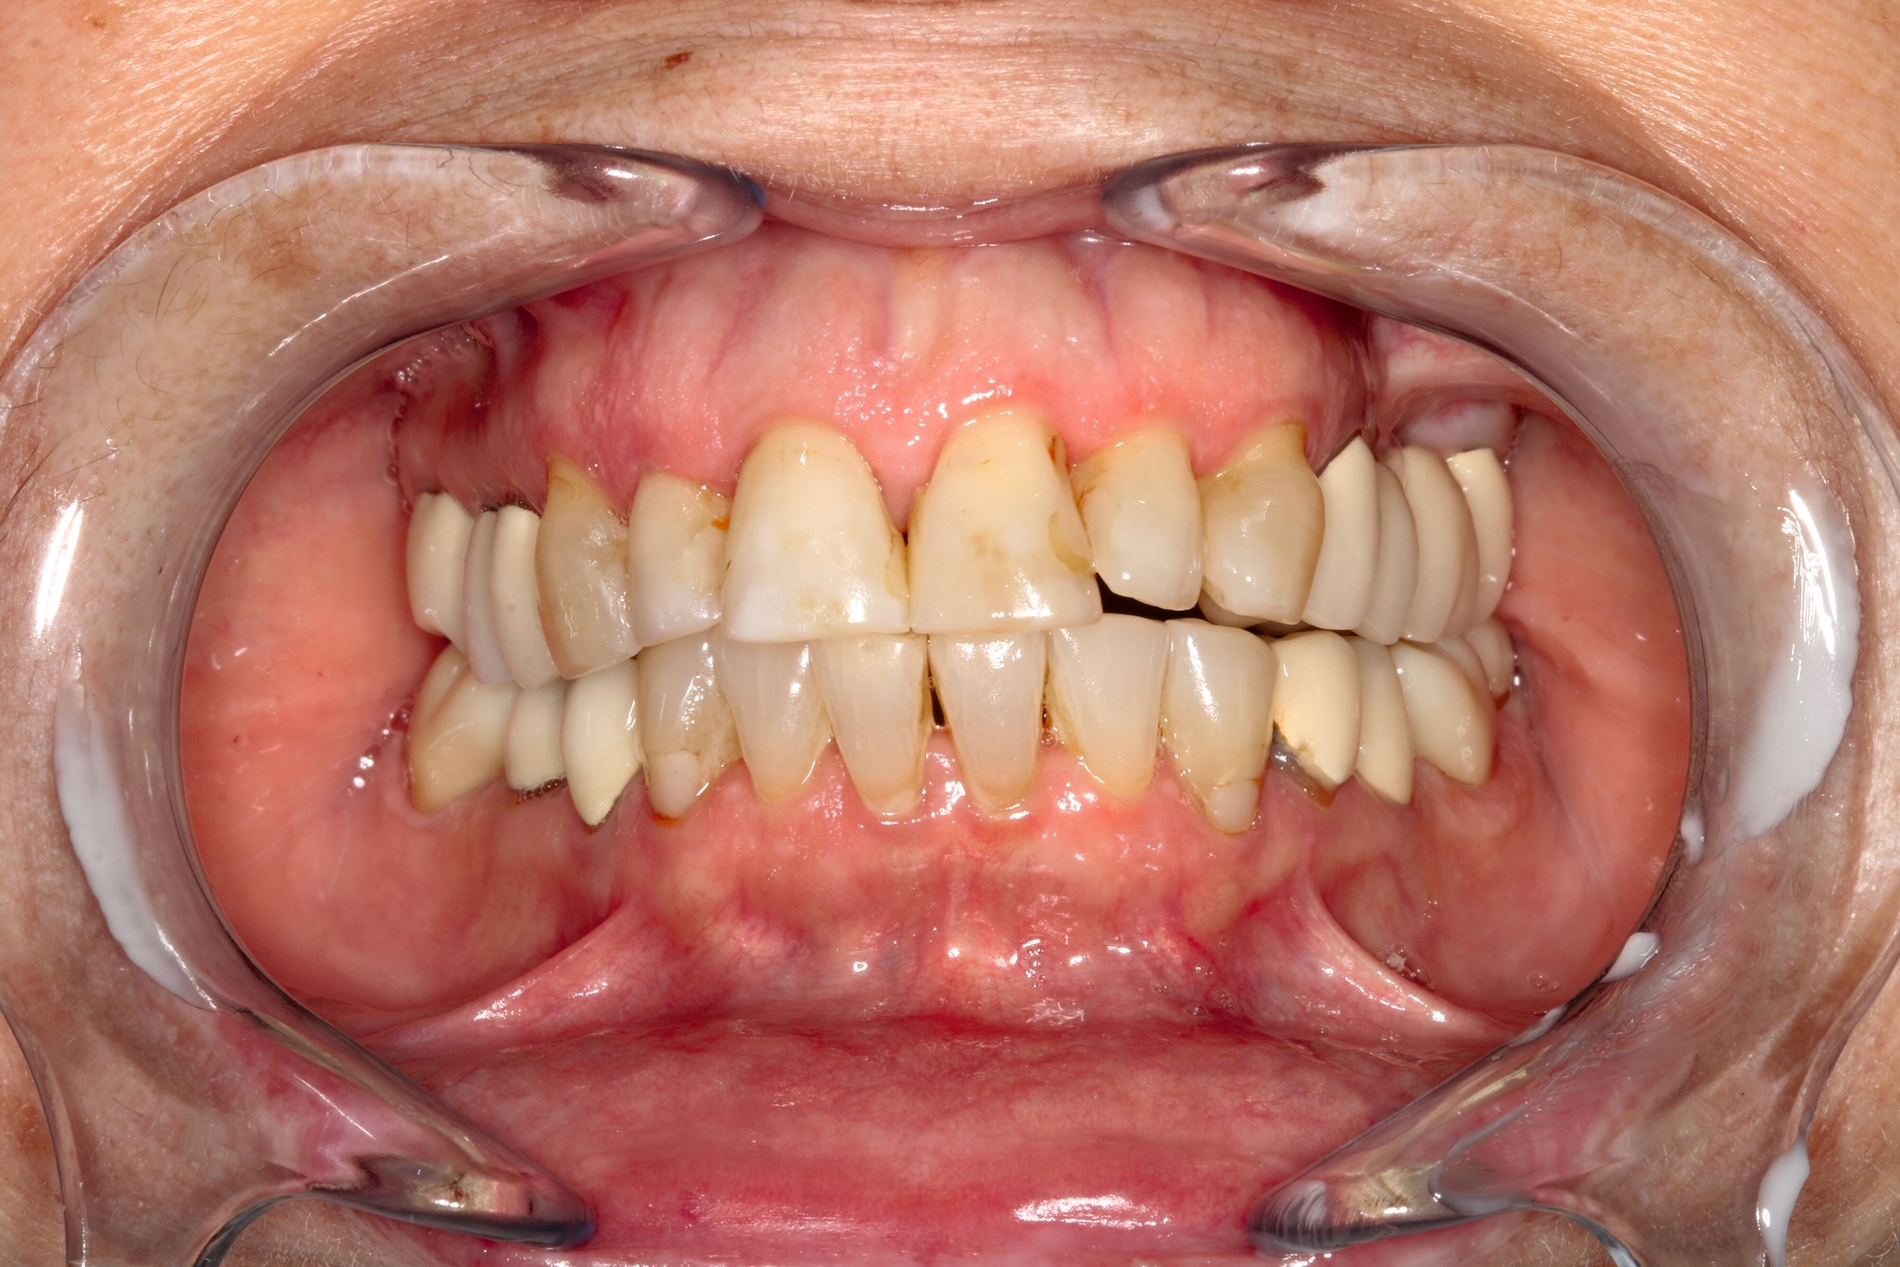

Bei der erneuten Vorstellung in der HNO-Abteilung etwa ein Jahr später berichtete die Patientin über eine seit Monaten bestehende Schwellung prämaxillär links sowie gelegentliche gelbliche Rhinorrhoe. Sie hatte zunächst eine niedergelassene HNO-Kollegin konsultiert, die eine DVT-Untersuchung durchführte, bei der eine Verschattung des linken Sinus maxillaris, verursacht durch eine überstopfte palatinale Wurzelfüllung am Zahn 26, nachgewiesen wurde (Abbildung 2).

Die Guttapercha-Füllung ragte dabei 7,2 mm in den Sinus maxillaris hinein. Die von der HNO-Ärztin veranlasste Begutachtung der DVT-Bilder durch einen niedergelassenen Zahnarzt ergab laut dessen Beurteilung keinen zahnärztlichen Handlungsbedarf. Bei bestehender Beschwerdesymptomatik (wie beschrieben) wurde die endoskopische Kieferhöhlenrevision links in Intubationsnarkose durchgeführt.

Hier wurde, neben einer klinischen Untersuchung, eine radiologische Diagnostik mittels OPG und DVT durchgeführt (Abbildung 3). Im Ergebnis manifestierte sich der dringende Verdacht, dass die überpresste Wurzelfüllung (Guttapercha-Stift/Sealer) die chronifizierte Pilzinfektion ausgelöst und unterhalten hatte. Daher wurde entschieden, den Zahn 26 zu extrahieren und gleichzeitig das überpresste Wurzelfüllmaterial zu entfernen.